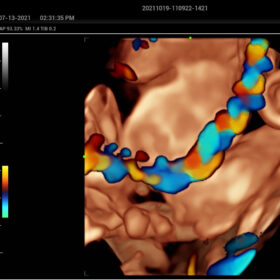

- HR-Flow Improving the hemodynamic presentation

Cardiovascular Solution

- Auto EF– Automatic measurement of ejection fraction by diastole/systole frames

- TTQA-Myocardial sychronization evaluation with quantitive analysis

- RIMT-RF data based real-time IMT measurement